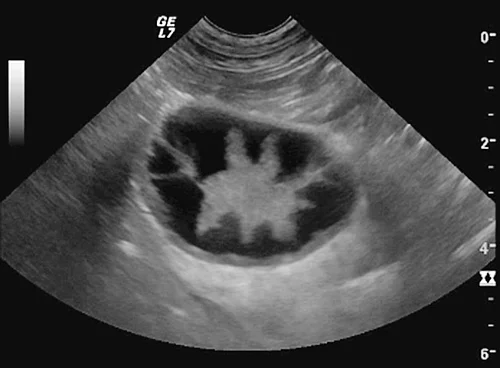

In der Literatur werden verschiedene Stadien der MZ beschrieben. Zu Beginn liegt sonografisch eine verdickte Mukosa entsprechend der pathohistologisch beschriebenen Hypertrophie vor. Die ansonsten dünne hyperechogene Linie der GB-Wand zeigt bei diesen Patienten eine raue, echoarme lumenwärts gelegene Schicht. Bei guter Bildauflösung können in der verdickten Mukosa feine echogene Lamellen erkannt werden (Abb. 2).

Im Lumen befindet sich häufig echogener Sludge, der wenig oder nicht mobil ist und der verdickten, echoarmen Mukosa aufliegt. Die GB ist im Frühstadium einer Mukozelenbildung unterschiedlich stark gefüllt. Im Verlauf nimmt die Füllung aufgrund der verminderten Motilität progressiv zu. So zeigten Hunde mit MZ 60 und 120 min nach Fütterung eine im Vergleich zu gesunden Hunden signifikant verminderte Ejektionsfraktion [13].